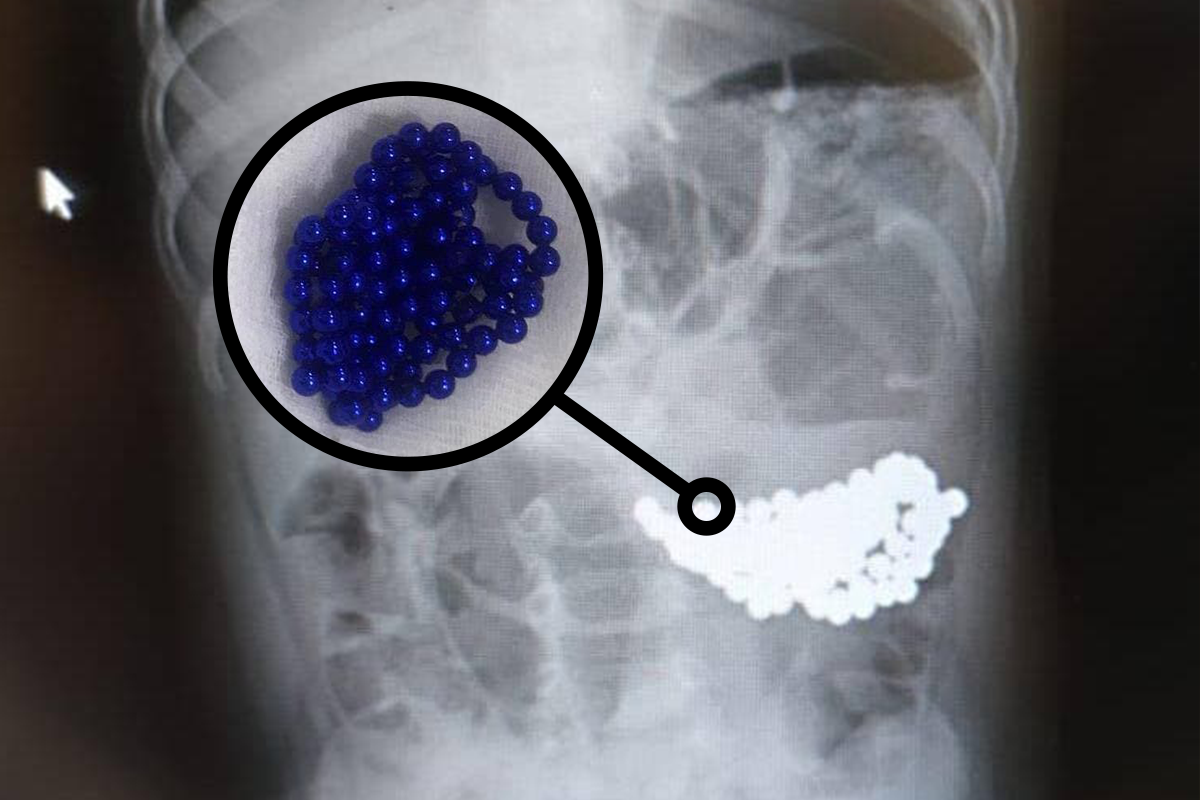

Магнитные шарики на рентгене: Интересные находки

Раздел: Картинки на заметку